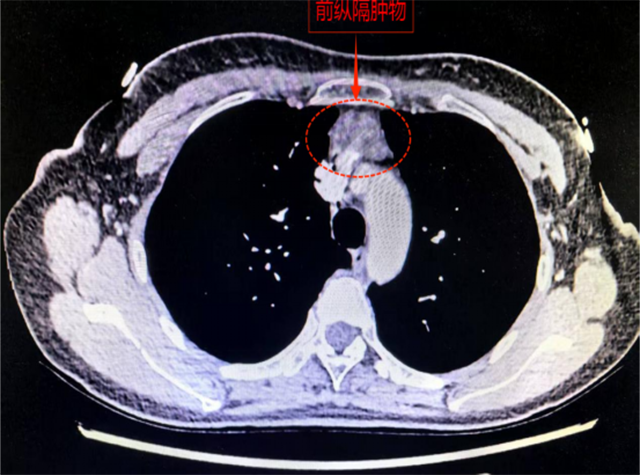

30岁的黄女士就面临着这样的挑战。一年前她在体检中发现前纵膈肿物,近期复查显示,该肿物已显著增大至3.5厘米。且肿物位置十分“刁钻”,紧贴胸骨与心脏之间,并与重要血管紧密相邻。若不及时处理,肿物可能继续增大,进而压迫心脏及大血管,甚至侵犯周围组织。

一旦这里长出肿物,尤其是位于胸骨后的前纵隔肿物,手术就变得异常棘手,它往往紧挨着心脏大血管生长,彻底切除肿瘤的同时,还要确保这些“生命通道”毫发无损。